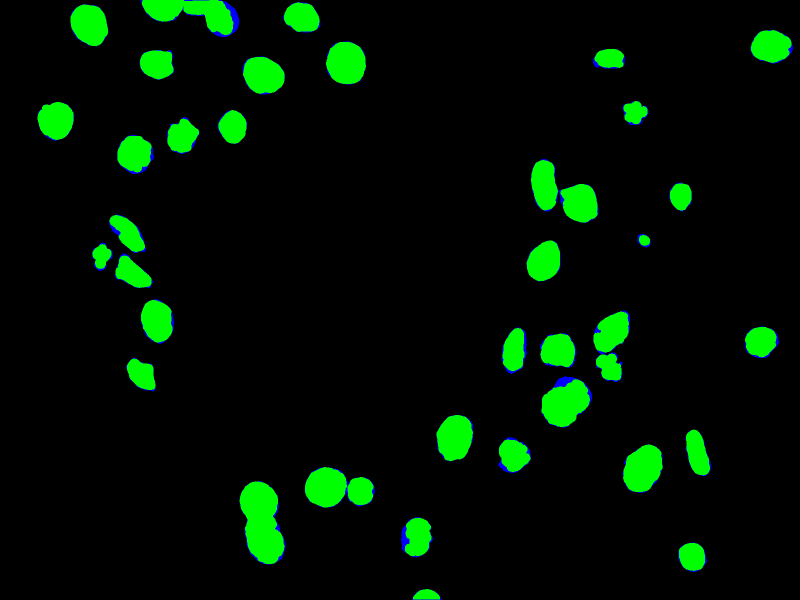

In order to illustrate this, Fig. 7 shows an example of IoU between the ground truth and the prediction of the network. The green pixels show the intersection between ground truth and prediction, and the blue pixels show the union between them.

Refer to caption

Figure 7. Overlapping between the intersection (green) and the union (blue) used to calculate the IoU